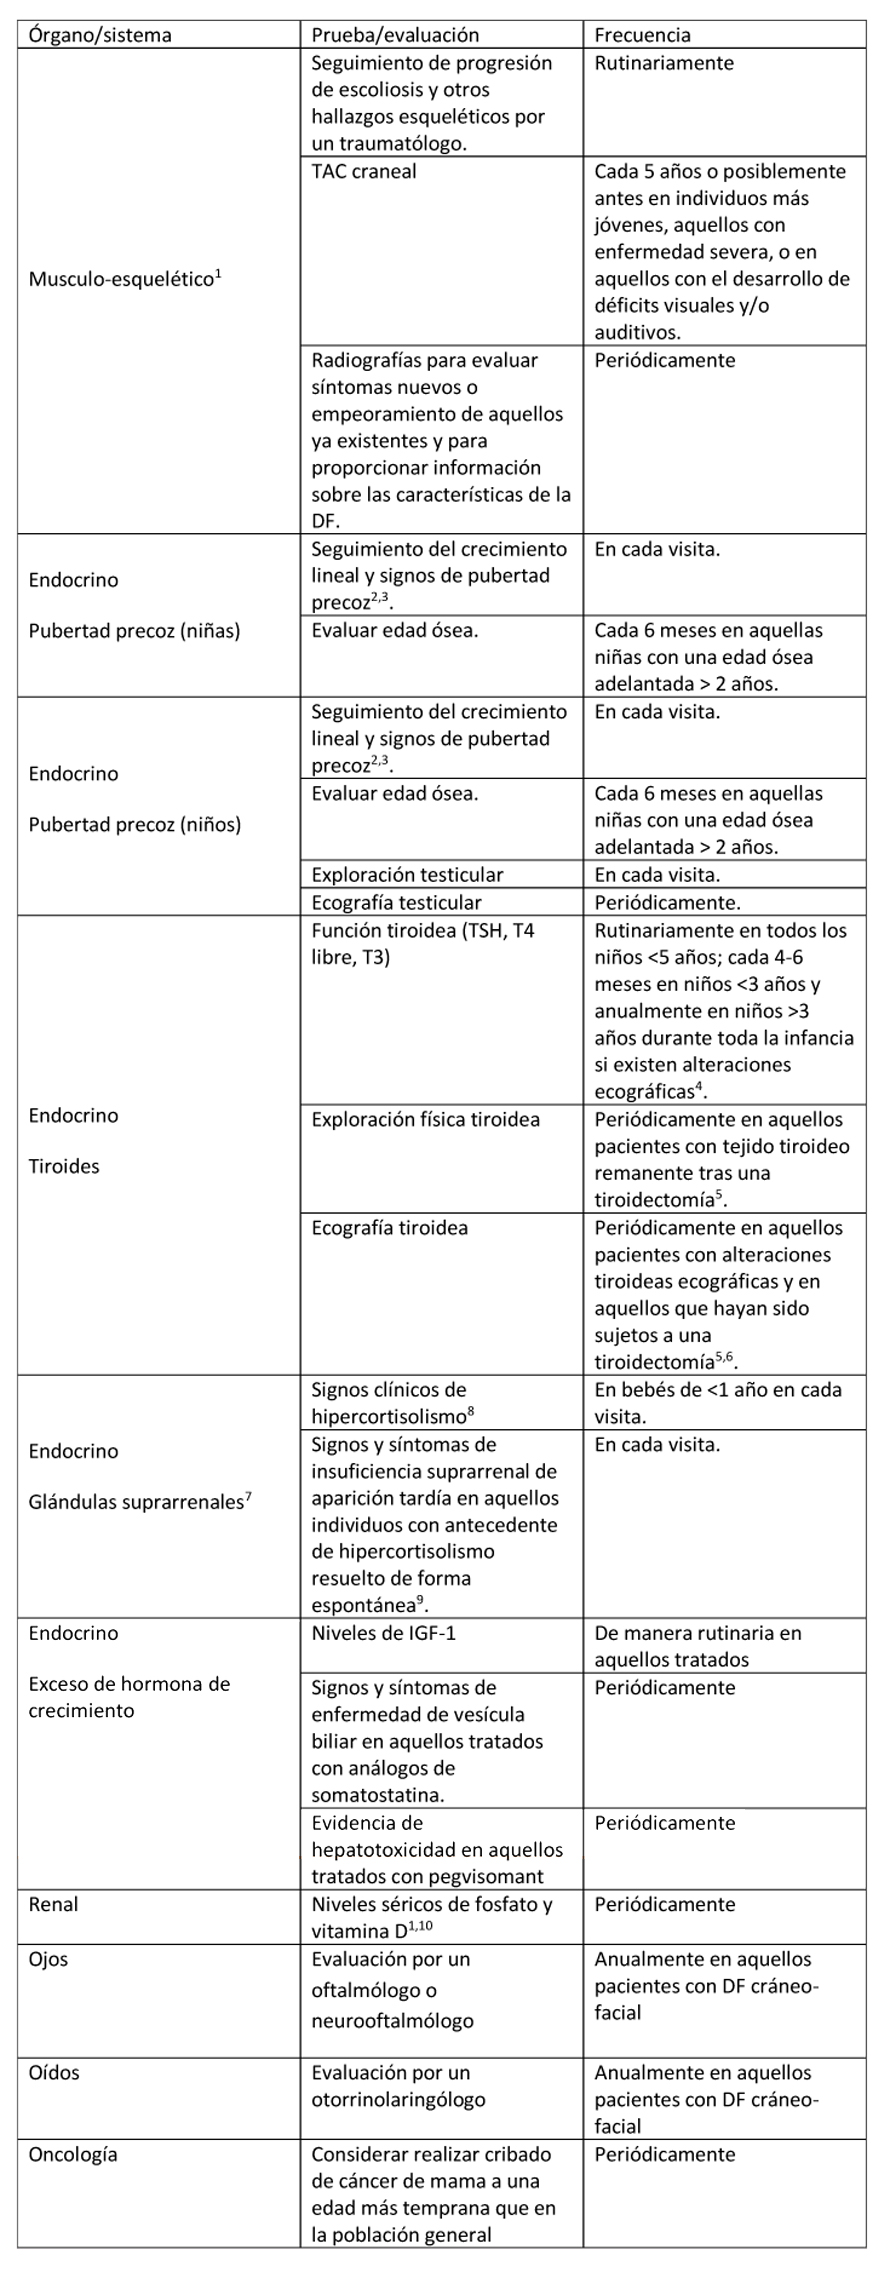

Tabla 2. Evaluaciones recomendadas tras el diagnóstico inicial en individuos con Displasia Fibrosa/Síndrome de McCune-Albright

(1) Ver Figura 3 en la que se exponen los estudios recomendados para evaluar el esqueleto tras el diagnóstico. ORL: sistema otorrinolaringológico; RGE: reflujo gastro-esofágico.

Tabla 6. Seguimiento recomendado para individuos con Displasia Fibrosa/Síndrome de McCune-Albright